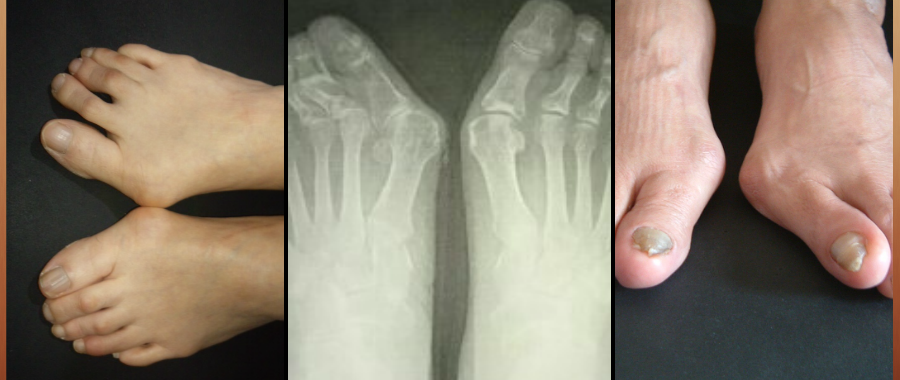

外反母趾、リウマチなどの変形、症状、痛みなどの悩みに

オーダーメイドシューズがお役に立ちます。

外反母趾、リウマチなどの変形、症状、

痛みなどの悩みに

外反母趾の害は

外反母趾だけに止まりません。